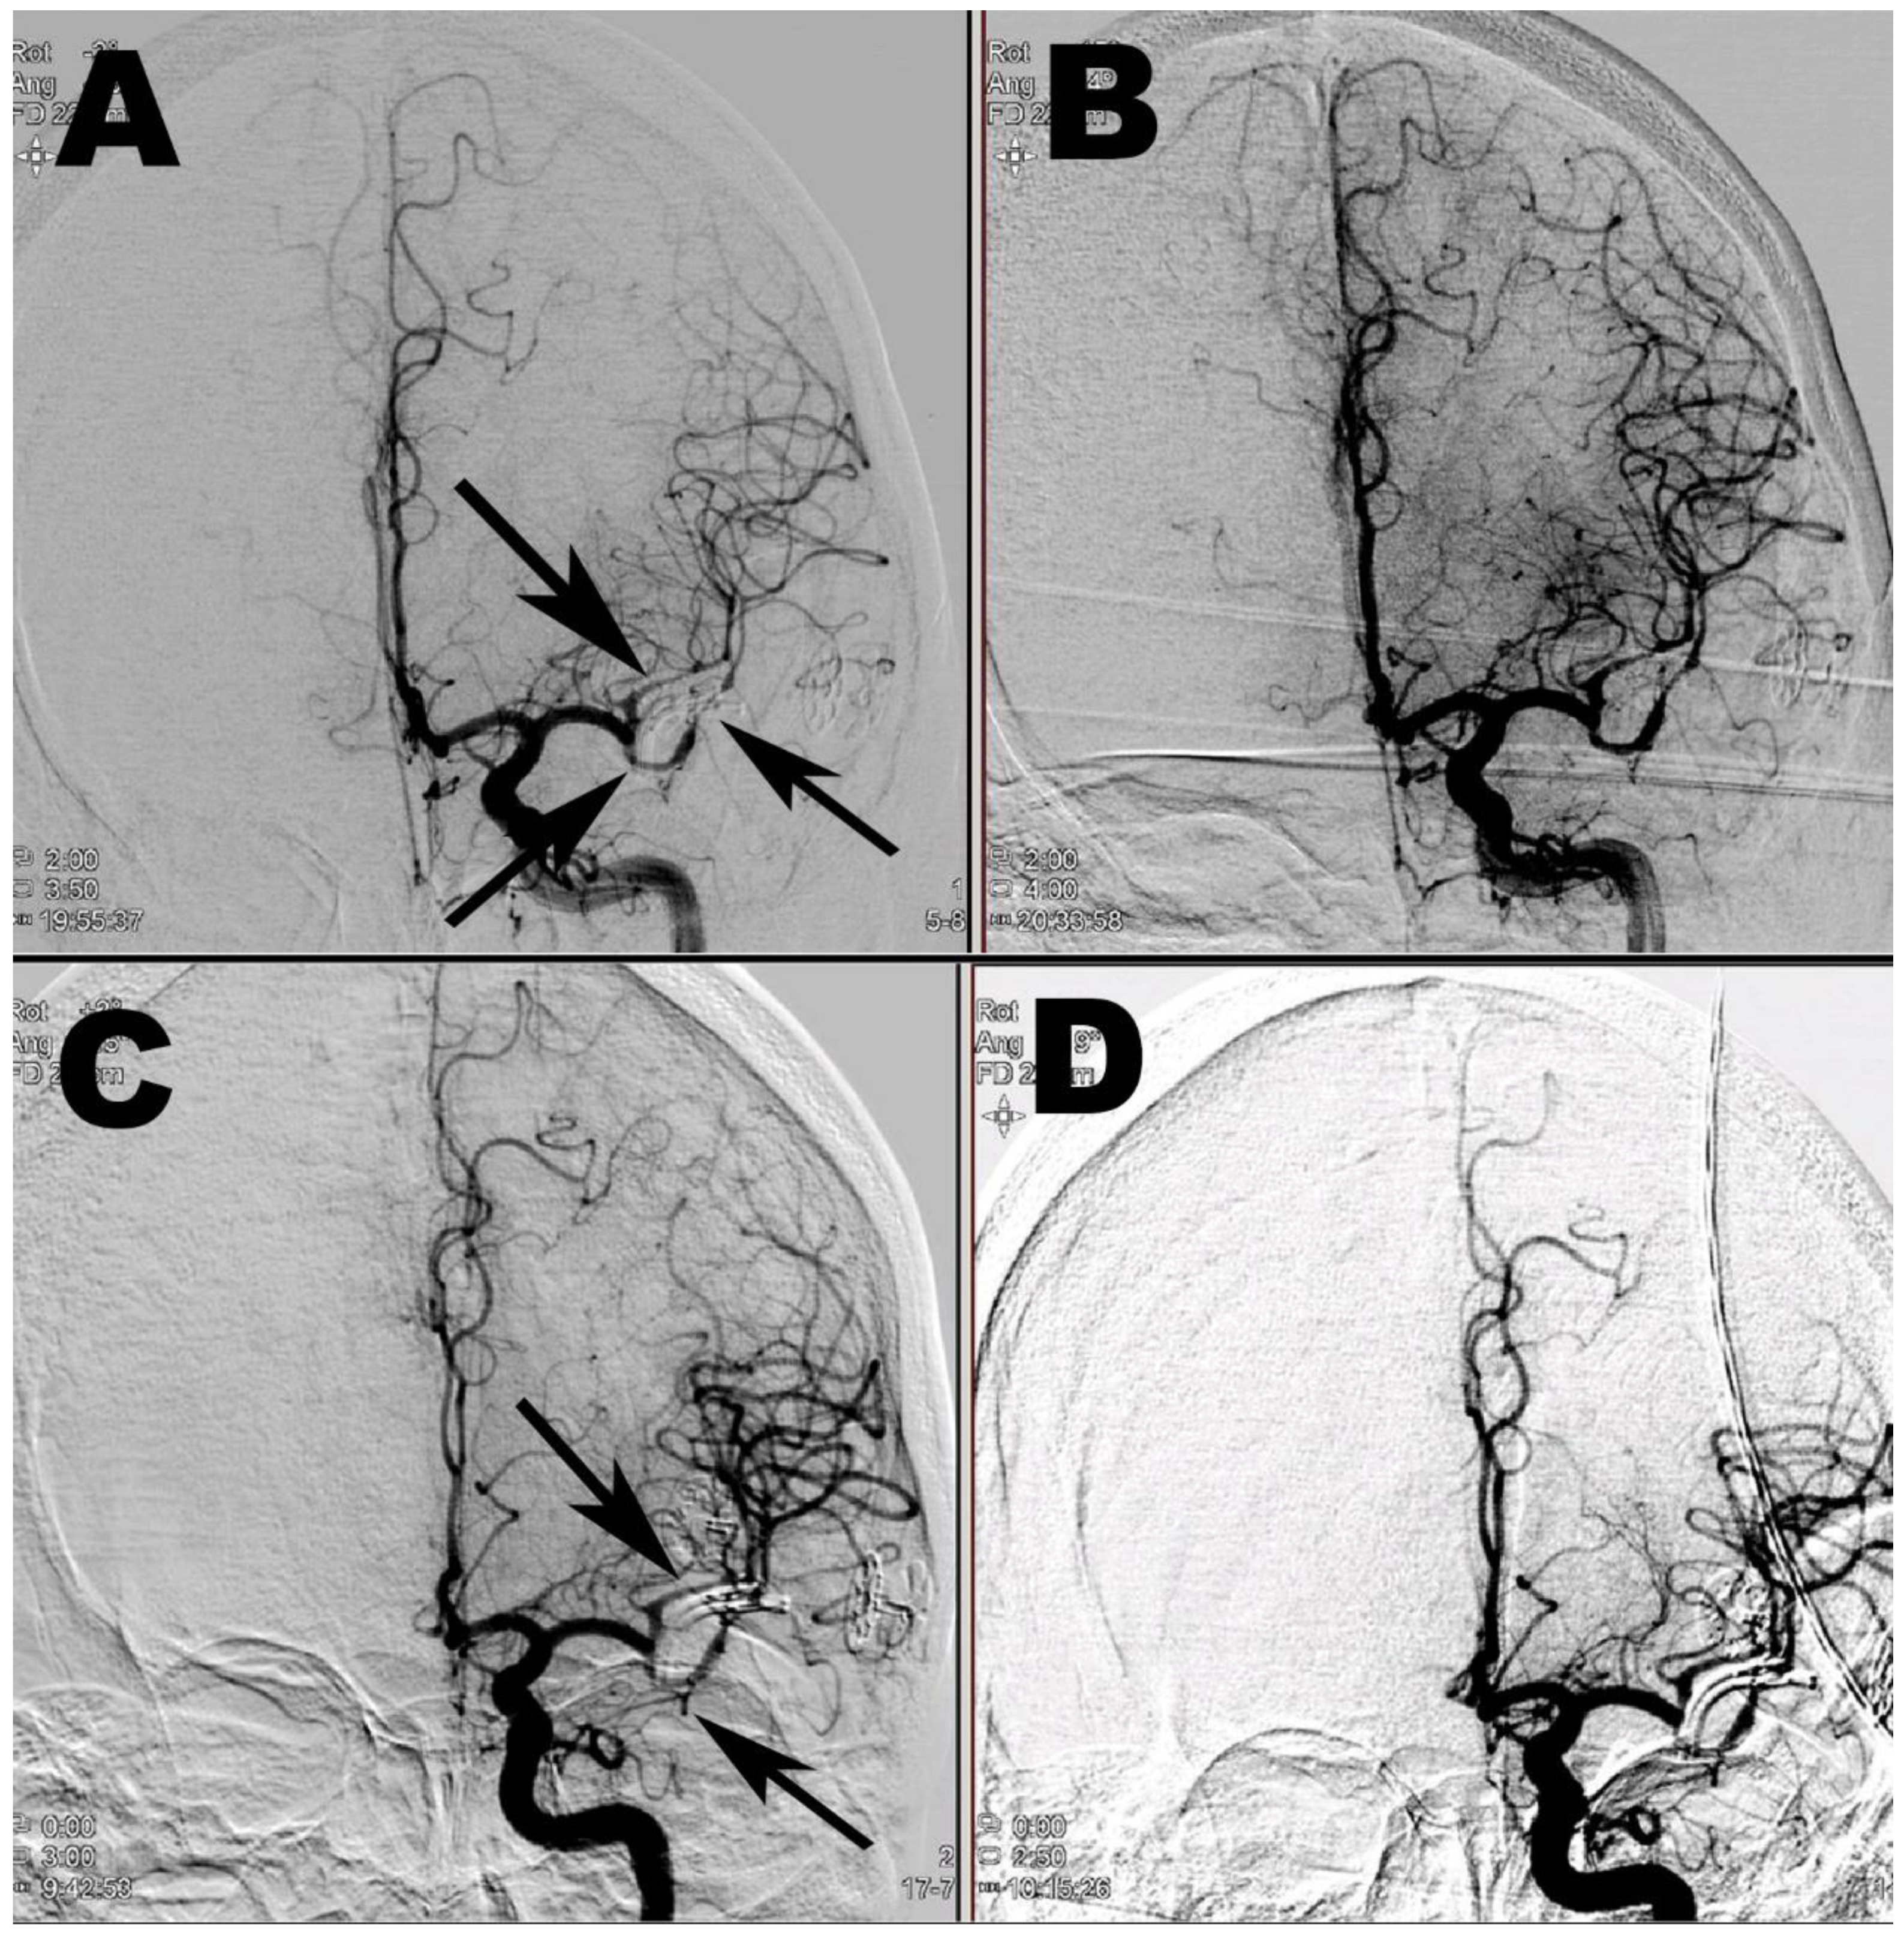

2. Case Report 1

3. Case Report 2